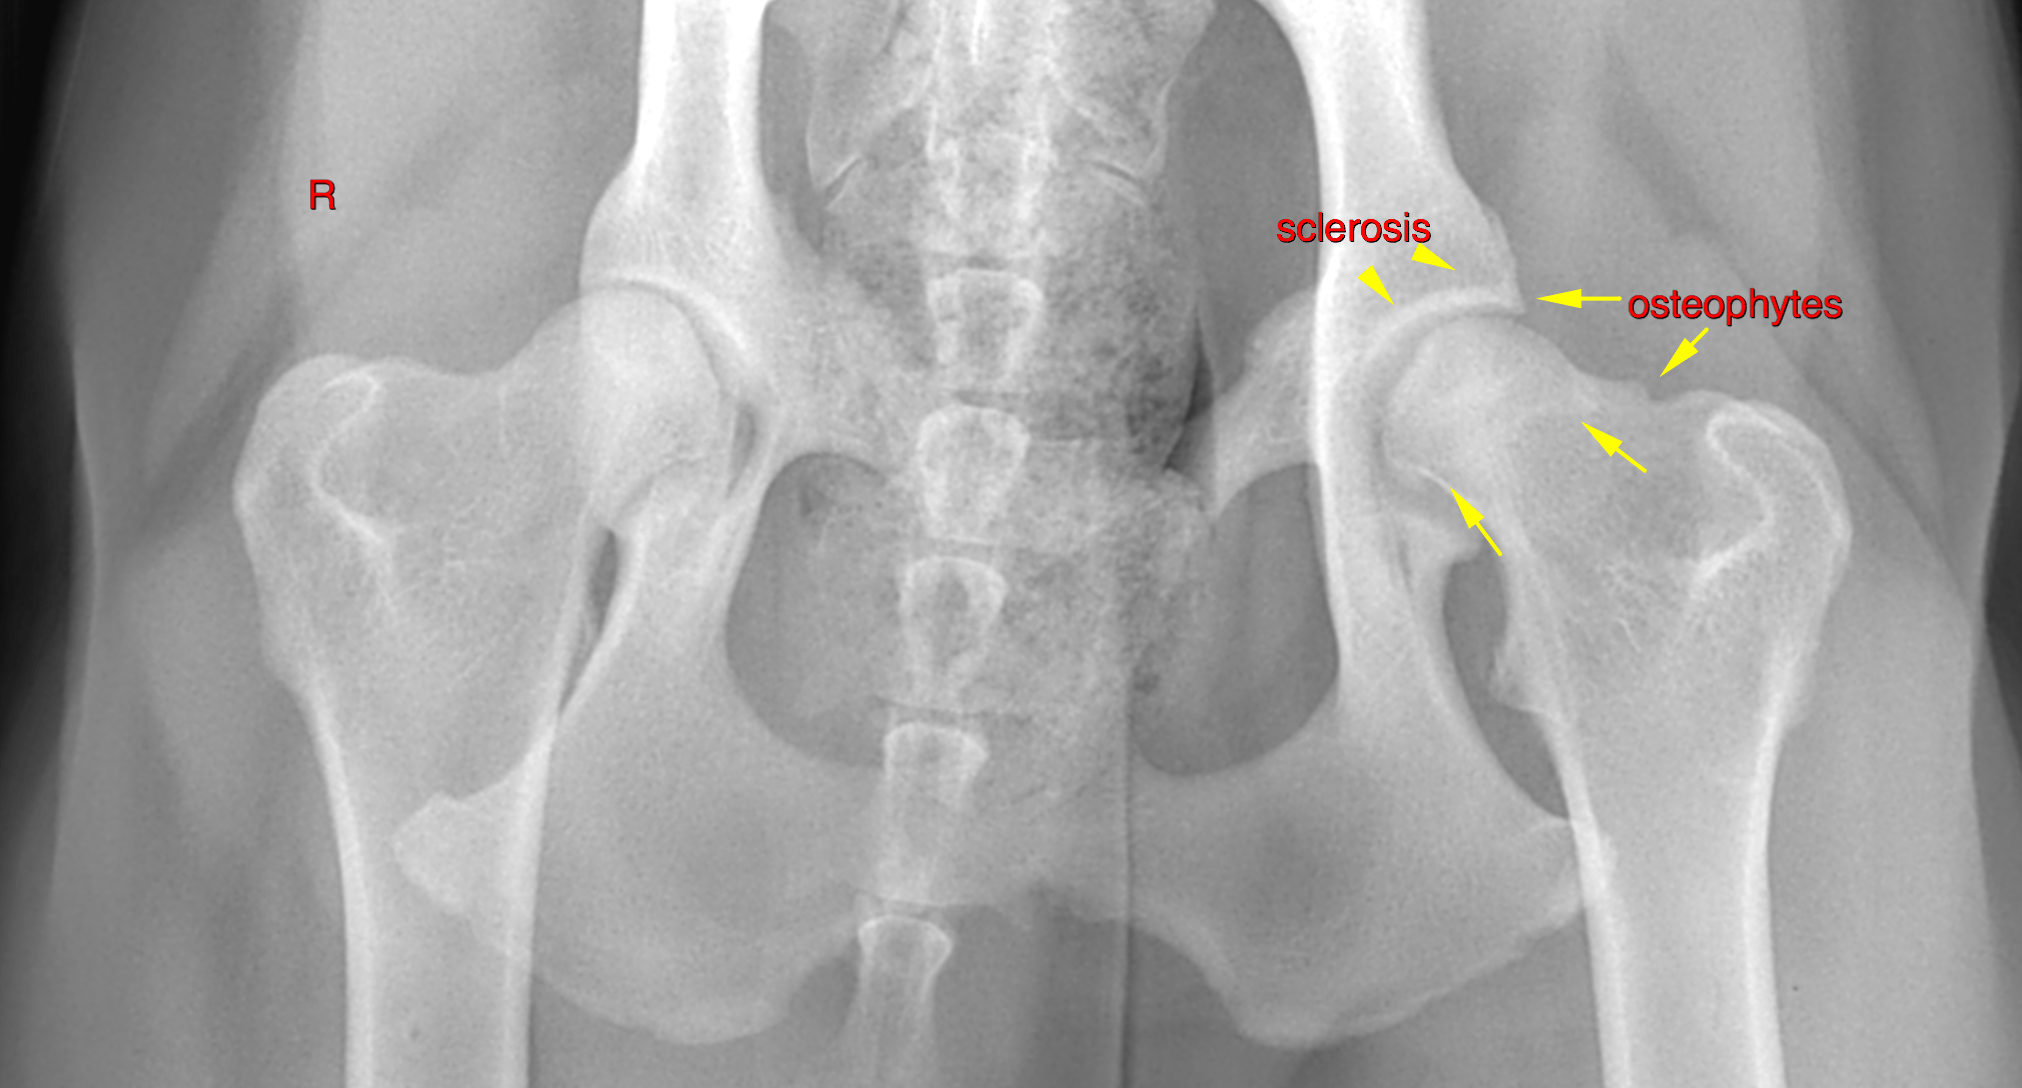

Hip dysplasia is perhaps the most well-known problem associated with the Coxofemoral Joint Dog. It is a hereditary condition where the ball and socket do not fit together properly, leading to laxity (looseness) in the joint.

Over time, this laxity causes the bones to rub and grind, resulting in cartilage deterioration and, eventually, painful osteoarthritis (OA). While common in large breeds like German Shepherds and Labradors, any dog can be affected.